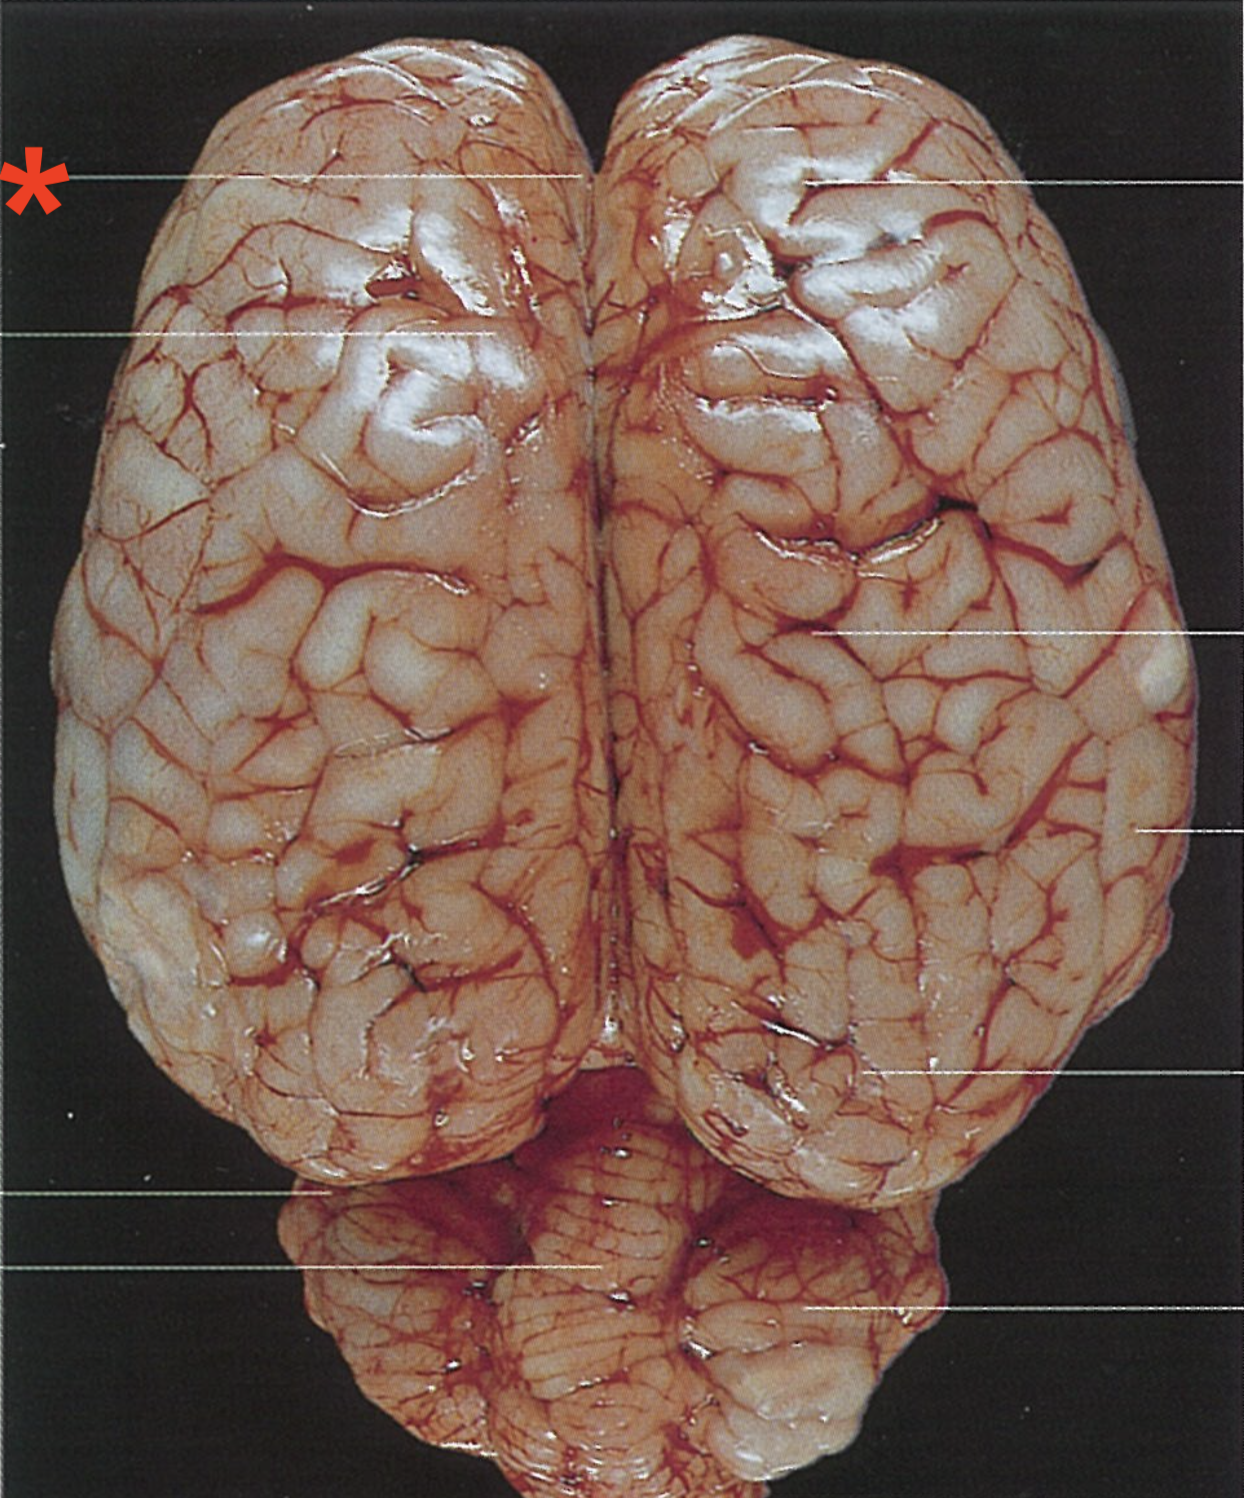

What is the telencephalon composed of?

Paired cerebral hemispheres

Longitudinal cerebral fissure

Frontal lobe

Cruciate fissure

Parietal lobe

Temporal lobe

Occipital lobe

What separates the two hemispheres of the telencephalon

Cerebral longitudinal fissure

What are the elevated bands found on the surface of the telencephalon hemispheres?

Gyri cerebri

What separates the gyri cerebri?

Sulci cerebri